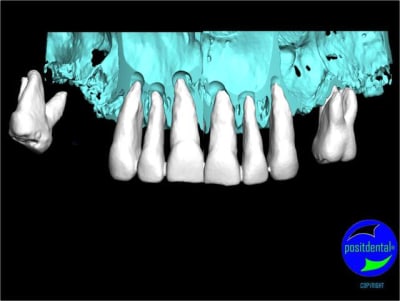

3D maxillaire inférieur et photo

Mci - Eugenol